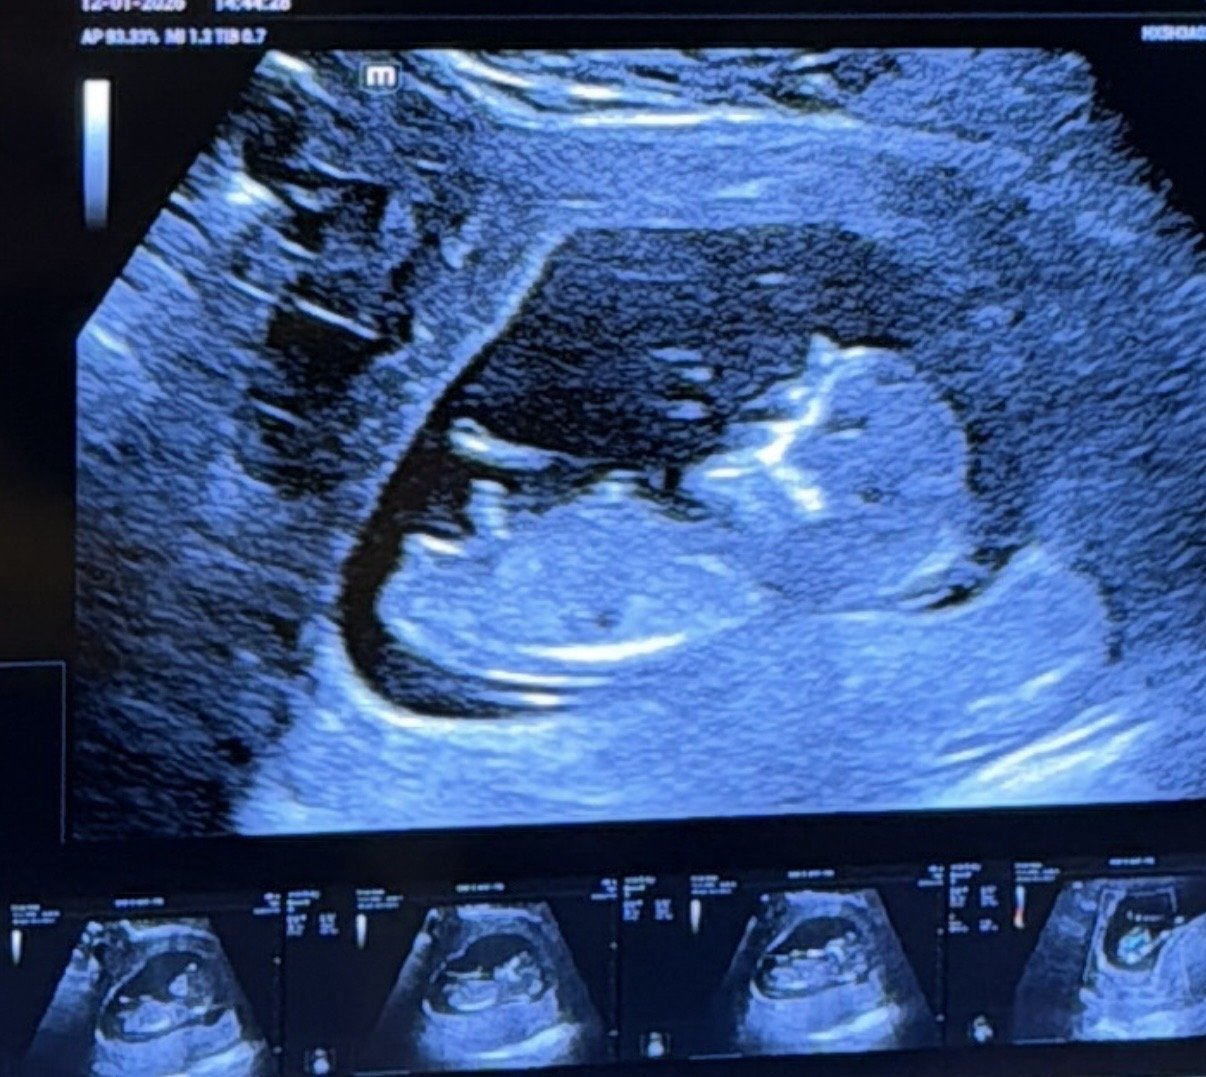

Здравейте, преди 2 седмици бях на преглед и доктора каза ,че се крие ,но му прилича на момиче. Вчера бях пак и ми каза ,че е момче вече са били влезнали тестисите надолу и се вижда хубаво. Аз някак не мога да повярвам и не съм на 100% сигурна прикачвам снимка. Ориентирам ви по това ,че това е дупето и двете крачета между тях се вижда нещо подобно на тестиси ,но не знам. Какво мислите вие? Ще се побъркам до следващия преглед...

Здравейте, какъв е полът според вас? ☺ Снимката е от 16+0 и не успяха да кажат със сигурност

Какво мислите че е момче или момиче